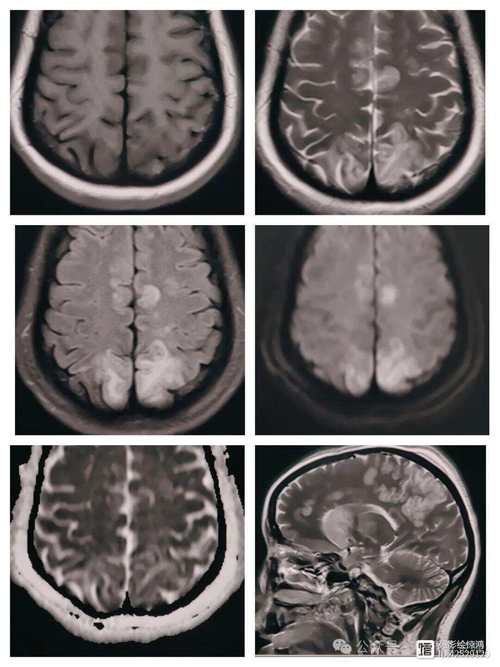

脑白质病变,在影像学上(如CT或MRI)通常表现为“脑白质高信号”(White Matter Hyperintensities, WMH),它不是一种疾病,而是一种影像学表现,是多种因素导致的大脑白质发生的一种慢性、弥漫性改变。

- 脑梗可以加重脑白质病变: 一次脑梗(尤其是小血管梗塞)会直接破坏白质,在MRI上表现为一个明确的“梗死灶”,这本身就是脑白质病变的一部分。

| 诊断依据 | 临床症状 + 影像学(MRI/CT)上明确的梗死灶 | 影像学(MRI)上白质区域的弥漫性高信号 |